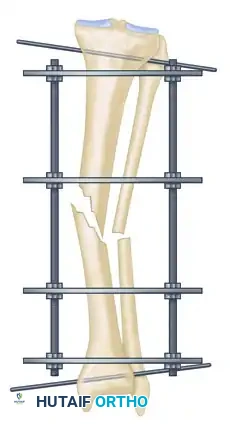

The management of complex, comminuted, or open tibial shaft fractures presents a formidable challenge to the orthopedic surgeon. The Ilizarov external fixation system, pioneered by Professor Gavriil Ilizarov, revolutionized the treatment of these injuries by introducing the concept of the tension-stress effect. Unlike rigid internal fixation, the Ilizarov circular frame utilizes tensioned fine wires to provide exceptional shear and torsional stability while permitting controlled axial micromotion. This unique biomechanical environment stimulates robust secondary bone healing (callus formation) without the need for extensive soft tissue stripping at the fracture site.

The efficacy of the Ilizarov frame relies on the precise geometric arrangement of rings and tensioned wires. Standard fine wires (1.5 mm to 1.8 mm) are tensioned to 110–130 kg, transforming them from flexible filaments into rigid beams capable of supporting physiological loads.

Step 3: Multi-Planar Fracture Reduction Using Olive Wires

Olive wires (wires with a small metal bead or "olive" forged into them) are powerful tools for translating bone fragments and achieving final reduction.

- Coronal Plane Correction: Use arched olive wires for final fracture reduction. For residual displacement in the coronal plane, place an olive wire in a transverse fashion (ensuring it passes through a safe anatomical zone).

- Apply tension to the wire without securing it tightly to the frame on the opposite side. The tensioner will pull the olive—and consequently the bone fragment—toward the tensioner, correcting the translation.

- Use continuous image intensification to ensure adequate reduction is achieved without over-translating the fragment.

- Once adequate correction is obtained in the coronal plane, secure the wire to the frame on the olive side.

- Sagittal Plane Correction: If further correction is required in the sagittal plane, connect another olive wire in an arched fashion. Tensioning this arched wire will impart a directional force vector to the bone, achieving final sagittal alignment.